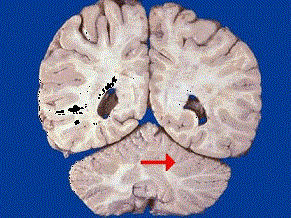

如图箭头所示为大脑哪个部位 ( ) A、脑干B、额叶C、枕叶D、小脑E、顶叶

问题 如图箭头所示为大脑哪个部位 ( )

选项 A、脑干 B、额叶 C、枕叶 D、小脑 E、顶叶

答案 D